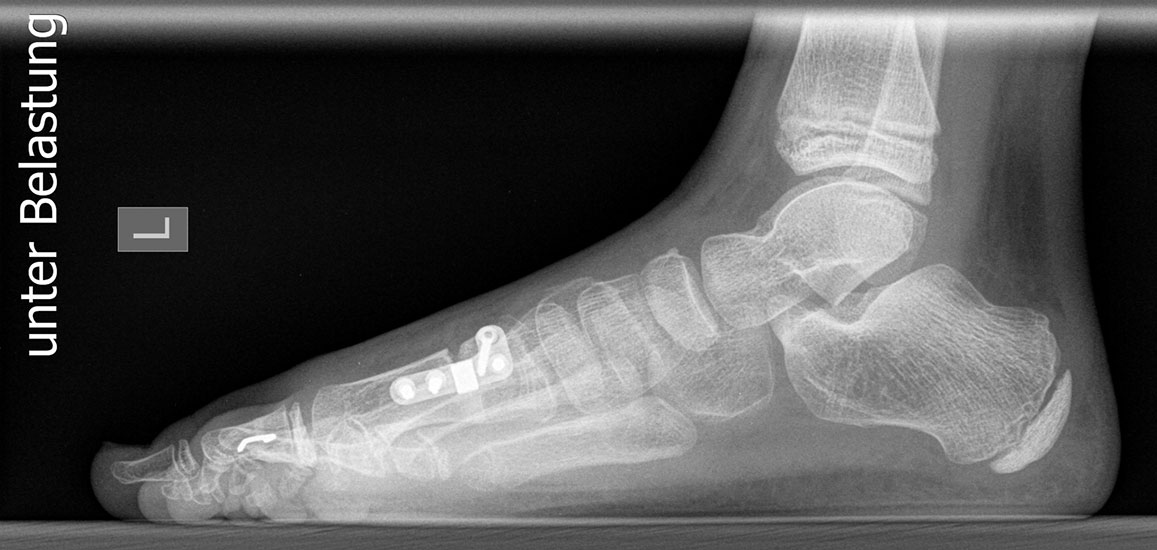

Röntgen

Standard ist die belastete Röntgenaufnahme des Fußes dorso-plantar und seitlich. Günstig ist eine Röhrenkippung von 10°-20°, um die Gelenke der Lisfranc-Linie einsehen zu können.

Ergänzend kann eine Schrägaufnahme hilfreich sein. Bei Metatarsalgien oder Pathologien der Sesambeine liefert die Sprinteraufnahme zusätzliche Informationen. Bei einer Pes planovalgus Fehlstellung wird ergänzend ein Saltzman view durchgeführt.

Bezüglich der Operationstechniken wird von früher häufig durchgeführten alleinigen Weich­teileingriffen am Großzehengrundgelenk aufgrund hoher Rezidivraten abgeraten 15. Die Operation nach Mc Bride mit lateralem Release, Exzision des lateralen Sesambeins, Abtragen der Pseudoexostose, Sehnenetransfer des M. adductor hallucis und mediale Kapselraffung zeigte unbefriedigende Mittel- und Langzeitergebnisse 16. Die Cerclage fibreux (mediale Kapselraffung) und das laterale Kapselrelease wird heute in Kombination mit einem knöchernen Eingriff angewendet. Bezüglich des Einsatzes von minimalinvasiven Operations­techniken vor Wachstumsabschluss liegen bisher keine Daten vor. Alle Osteotomien lassen sich nach Bedarf miteinander kombinieren. Es ist darauf zu achten, dass Osteotomien keine offenen Wachstumsfugen verletzen.

• Nach Schluss der Wachstumsfugen: TMT I Arthrodese nach Lapidus 2425